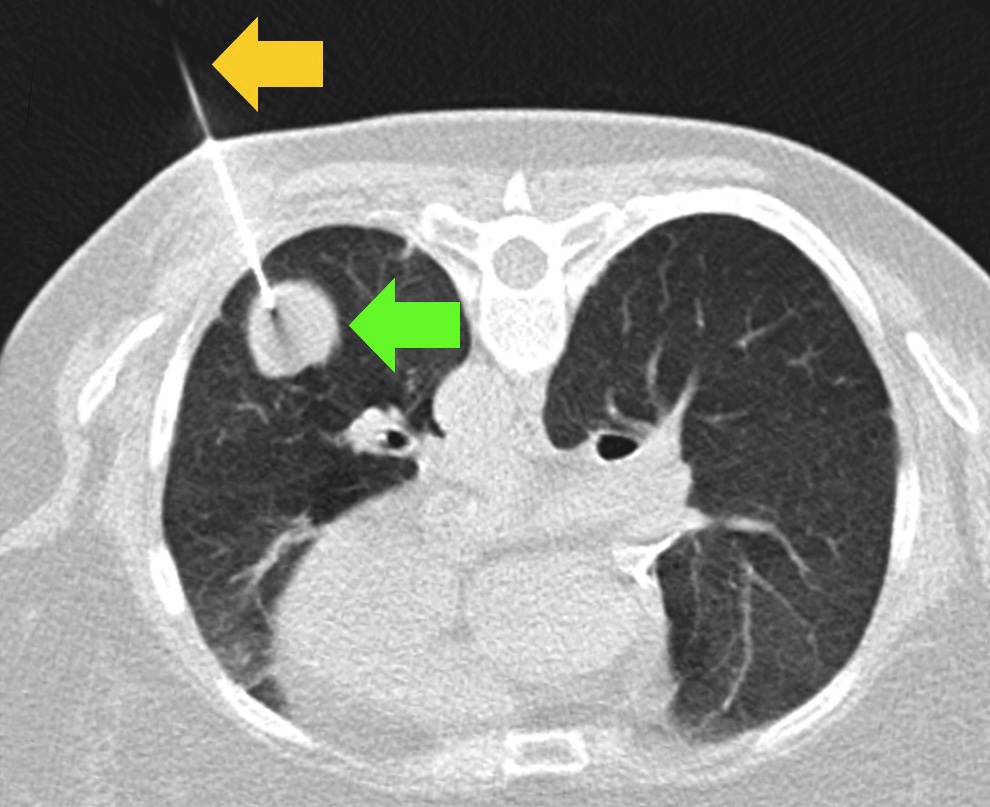

Ung thư phổi đứng đầu về tỷ lệ tử vong toàn cầu. Theo báo cáo từ GlOBOCAN, có tới hơn 70% bệnh nhân ung thư phổi được chẩn đoán khi đã ở giai đoạn muộn (giai đoạn 3 hoặc 4).

Nguyên nhân là do cấu trúc phổi có nhiều ngóc ngách và bị các xương sườn che chắn nên phương pháp chụp X quang ngực thẳng thông thường rất khó phát hiện các nốt đơn độc có kích thước dưới 10mm. Những tổn thương nằm ở vị trí khuất thường chỉ được nhìn thấy rõ ràng qua chụp cắt lớp vi tính (CT) liều thấp, một kỹ thuật giúp giảm tỷ lệ tử vong do ung thư phổi tới 20% so với chụp X quang thông thường.